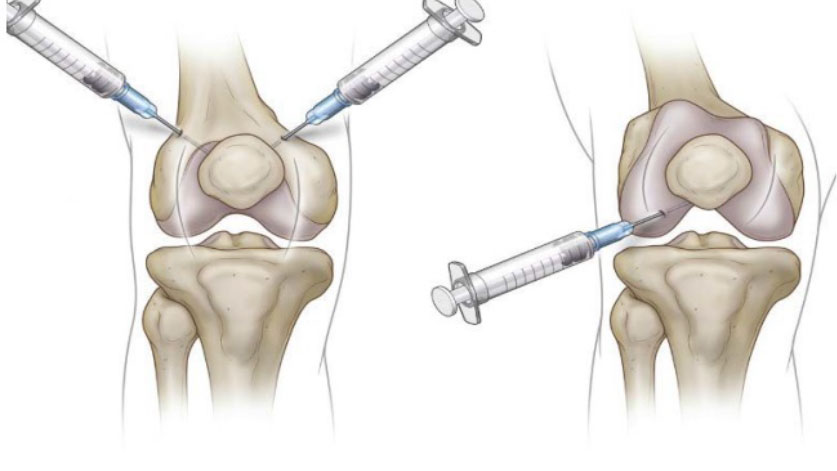

The product should be administered according to the frequency determined by the physician, according to the recommended frequency decision, such as 6-8-12 months. The number of injections is decision you and your doctor need to make. Treatment can be in both knees at the same time or at different times. Only medical professionals trained in accepted injection techniques for delivering agents to intra-articular synovial joint spaces should inject sodium hyaluronate for this application(Orthopedists.).

People with knee osteoarthritis who have tried non-invasive treatments (diet, exercise, and over-the-counter pain medications) but still have knee pain are suitable for use with this product. If you continue to experience pain, consult your doctor about the administered of the product.